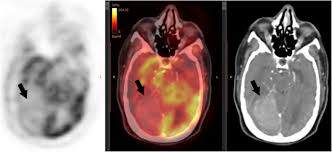

Pet Ct In Anal Cancer Indications And Limits Intechopen from www.intechopen.com The scanner detects diseased cells that absorb. Pet scans also prevent unnecessary surgeries and help suggest which cancer therapies are likely to be most effective for specific tumor types. Pet scans use radioactively tagged molecules (or tracers) to image a wide array of molecular processes and when detected by a pet scanner, the tracers help your doctor to see how well your organs and tissues are working. The pet scanner detects signals that are given off from the tracer. It also can let you and your doctors know if cancer treatment is working. Most pet scans use a type of radiolabeled sugar to detect the cancer, as the majority of cancers grow quickly and need sugar for that growth. Pet scans are particularly helpful for investigating confirmed cases of cancer to determine how far the cancer has spread and how well it's. Pet/ct, which is a combination of positron emission tomography (pet) with computerized tomography (ct), is a powerful, essential tool for cancer detection and diagnosis.

A new test called a psma pet scan makes these tumors easier to spot. Pet scanners work by detecting the radiation given off by a substance injected into your arm called a radiotracer as it collects in different parts of your body. The pet scan detects the concentrated psma tracer, pinpointing these tumors for more effective treatment. Pet/ct scans provide significantly more information than ct scans, and are far more reliable when diagnosing cancer. Pet/ct, which is a combination of positron emission tomography (pet) with computerized tomography (ct), is a powerful, essential tool for cancer detection and diagnosis.

Schedule A Pet Ct Scan University Radiology 20 Nj Locations from www.universityradiology.com A pet scan, which uses a small amount of radioactive material, can help show if an enlarged lymph node is cancerous and detect cancer cells throughout the body that may not be seen on a ct scan. Possible risks of a pet scan. The scanning table has a maximum weight capacity of 425 to 450 pounds, while the gantry has a diameter of only 27.5 inches. Positron emission tomography (pet) imaging scans use a radioactive tracer to check for signs of cancer, heart disease and brain disorders. For cancer and disease detection, the most commonly used nuclear scan is an fdg pet scan. Pet scans are most commonly used to detect: Pet/ct scans provide significantly more information than ct scans, and are far more reliable when diagnosing cancer. With that being said, not all cancers can be detected by pet.